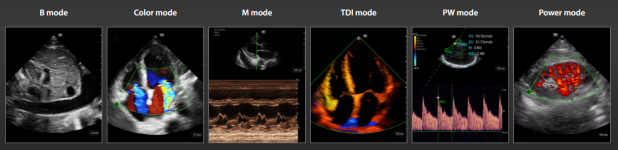

Modos de imagen

El transductor inalámbrico TE AIR ofrece imagenes en modos bidimensional 2D, Doppler Color, Modo M, Doppler Pulsado y Doppler Tisular (TDI)